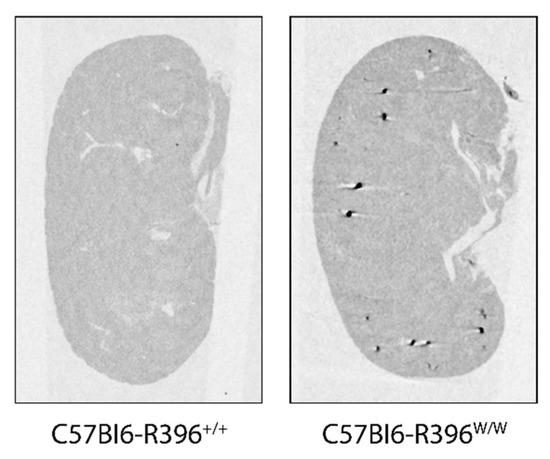

2.5. Microcomputed Tomography of Whole Kidneys